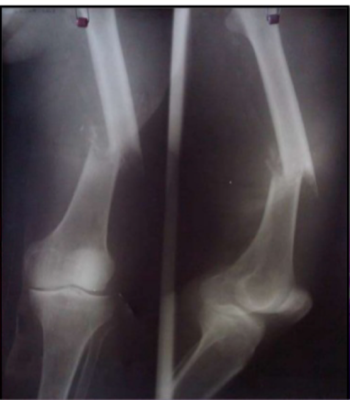

Paciente refiere que hace aproximadamente 1 mes sufre caída de una altura aproximada de 50 cm de impacto con superficie dura, presenta dolor de gran intensidad, tipo continuo localizado en muslo derecho, sin irradiación que aumenta con la deambulación. Paciente manifiesta que primero lo llevan a un "sobador" quien le da masajes en el área afectada agudizando el cuadro motivo por el cual acude a médico particular.

Answer

• Rotura de Rotula.

• Rotura de Tibia.

• Rotura de Perone.

• Fractura de Femur.